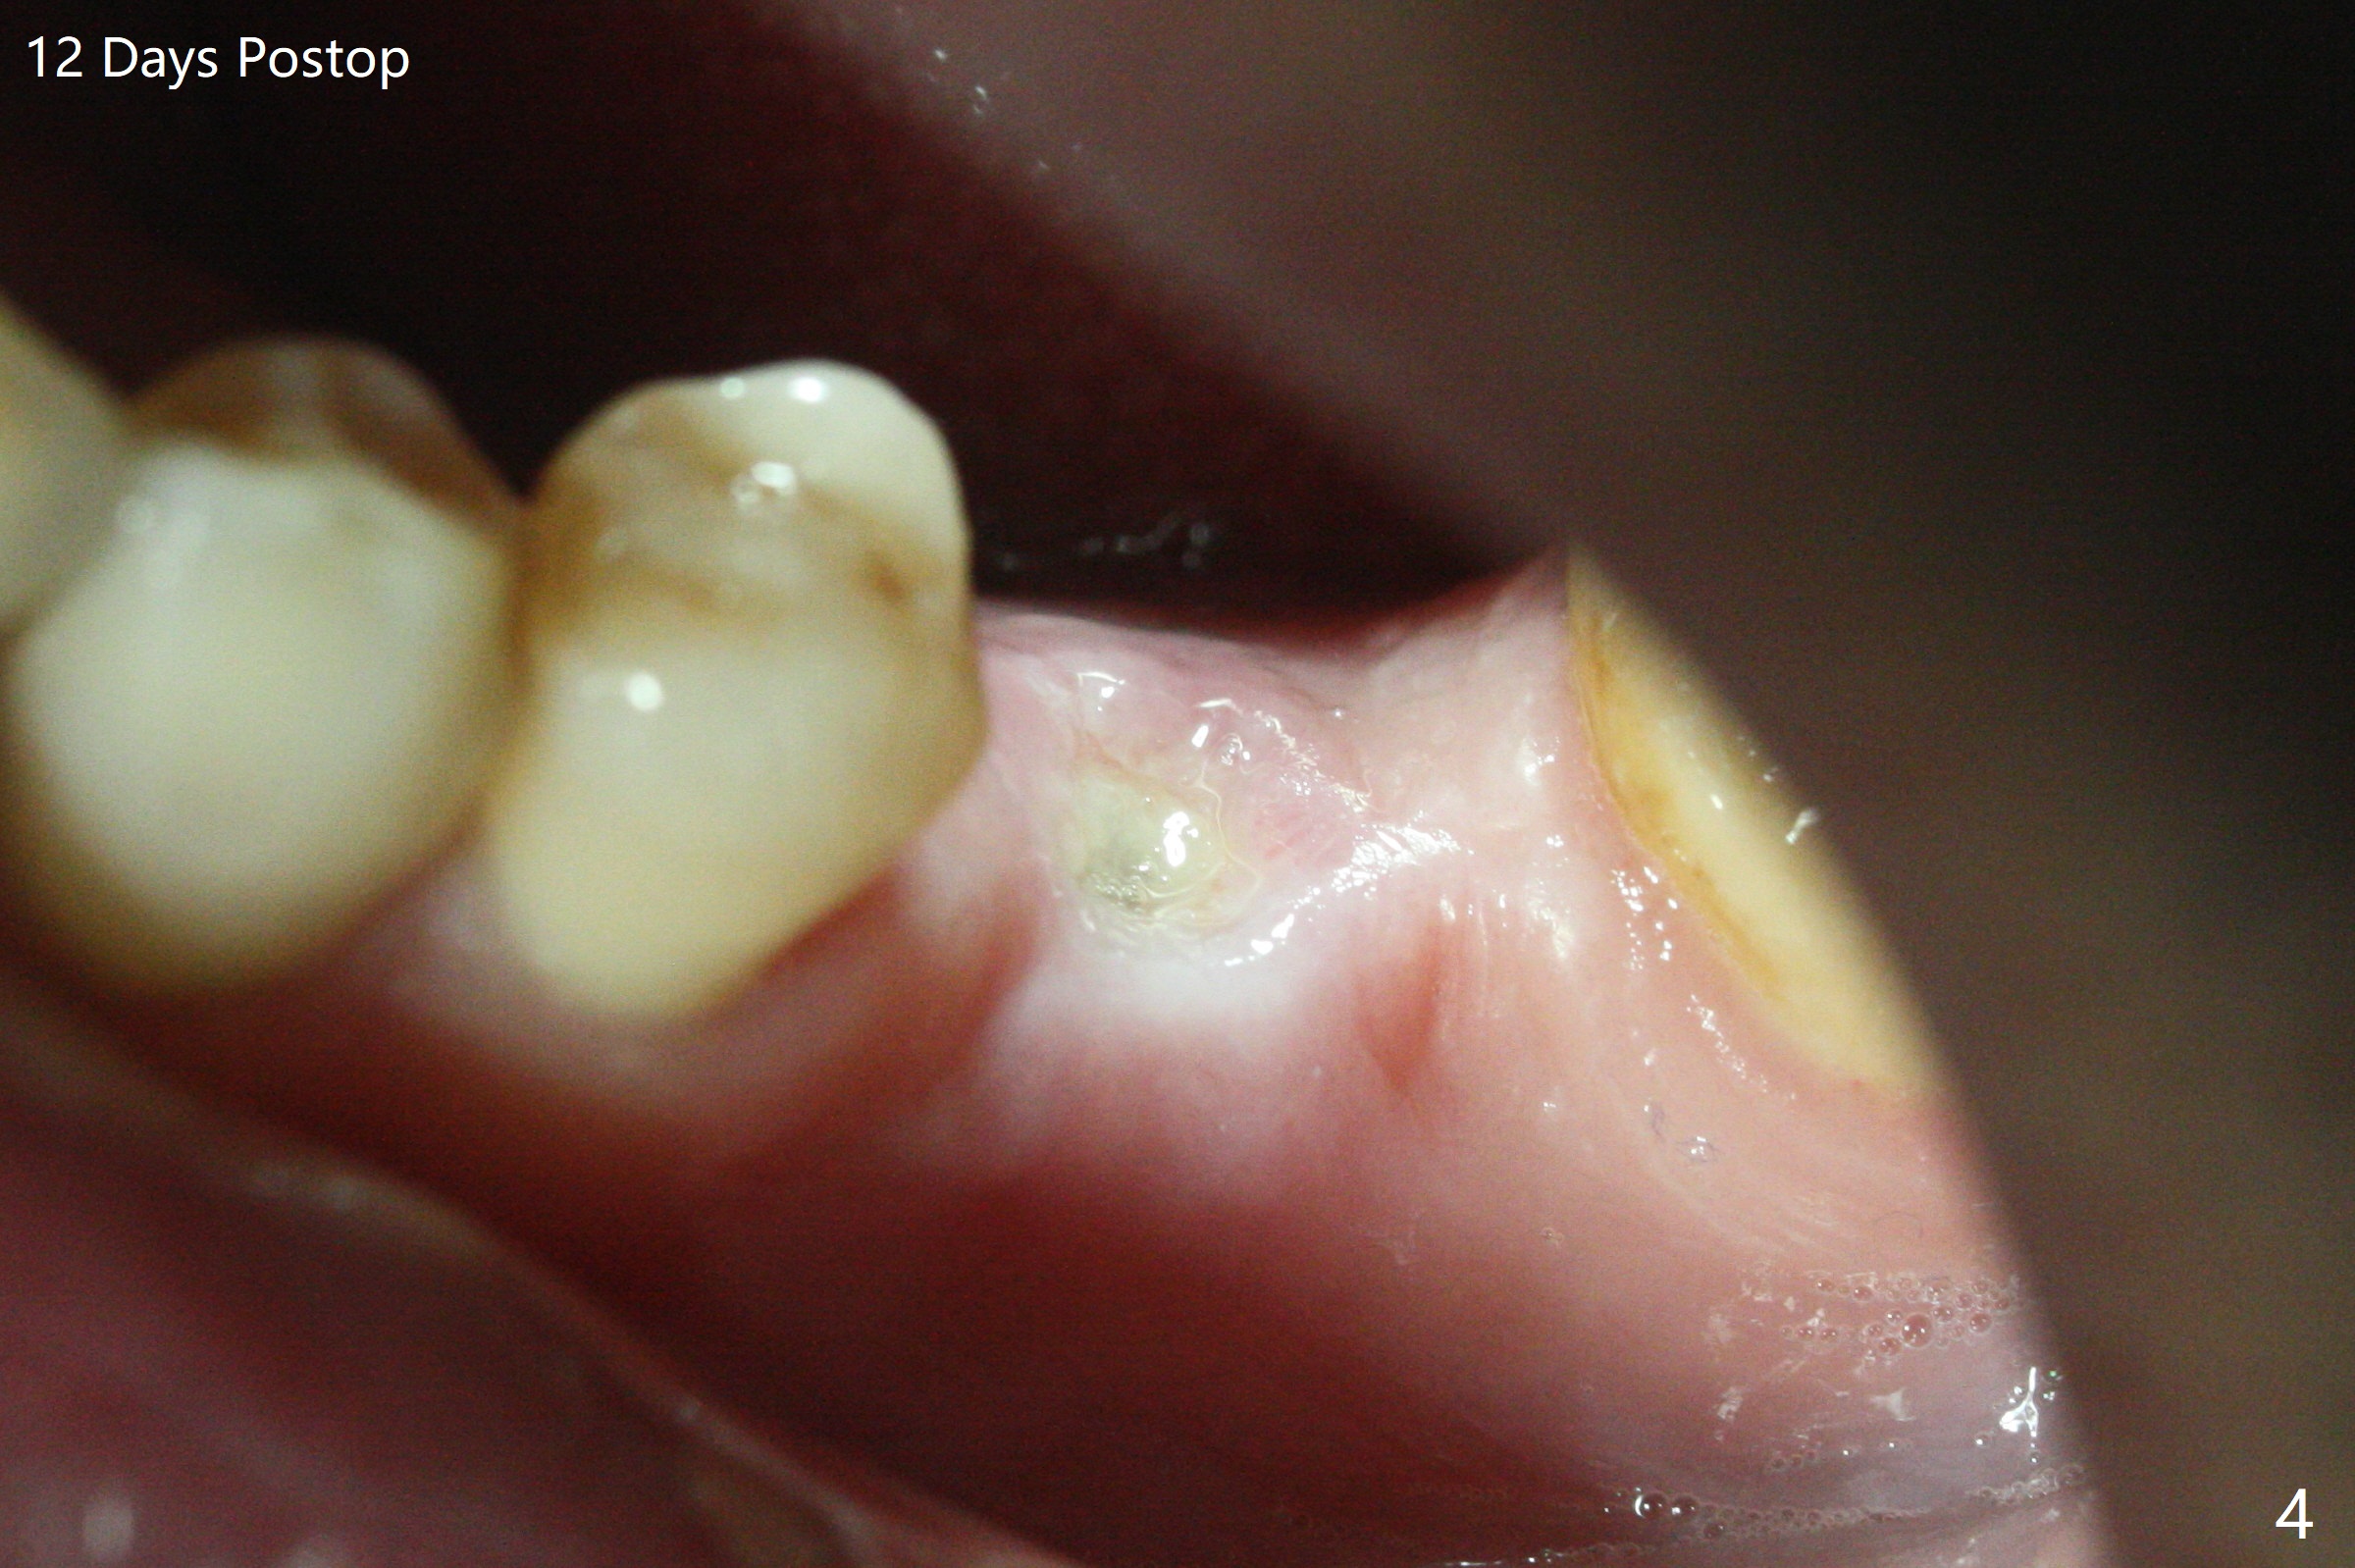

50岁男,左下6牙槽骨宽,但是骨密度低。开始使用导板和小钻头,植体(5x10毫米)扭力大,改用正常钻头,扭力仍高,使用功螺纹后,扭力~35Ncm;使用6毫米profile drill后,放置6x4(2)毫米愈合基台,后者好像与近中牙槽嵴接触(图一:*)。取出基台不顺利,接着放置5x5(3)毫米基台,无法拧紧,取出时,把植体带出来。最后把植体推入钻洞,没有任何扭力,放置愈合帽和Osteogen Plug,缝合(图二,三),牙周敷料,但愿能愈合。在骨质密度低时,放置不合适基台(太宽,太短),可能造成植体松动,脱落,失败。术后十二天牙周敷料脱落,伤口正在愈合(图四(曾经使用环形刀))。术后四个月植体仿佛已经整合(图五),切开放置6.2x5(3)毫米愈合基台,好像与近中牙槽嵴接触太紧(图六)。12天后放置修复基台,似乎就位(图七),其实我们使用取模帽放置基台,非常容易,取模也方便。基台牙冠就位也容易(图八)。螺丝拧紧25Ncm/厂家建议35Ncm。